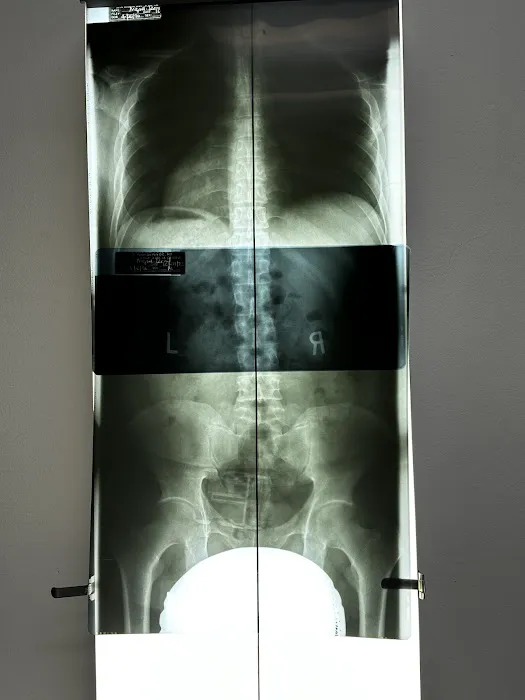

Thorough Diagnostic Assessments: A hallmark of their service is the initial in-depth assessment, including taking an X-ray "before starting any treatment to pinpoint exactly what needed to be fixed." This detailed approach ensures that treatments are precise and targeted to the root cause of the patient's condition.

Dr. Park's Exceptional Skill and Meticulous Approach: The most significant highlight is the expertise of Dr. Park, consistently lauded as "the Best!" Patients appreciate his "very thorough" initial assessment, including X-rays, to "pinpoint exactly what needed to be fixed." This detail-oriented approach ensures that treatments are incredibly precise and effective, leading to significant and lasting improvements, even for complex injuries.

Firstly, the expertise of Dr. Park, frequently lauded as "the Best!" and a "skilled, caring, and detail-oriented" practitioner, is a major draw for locals. In a city where health and wellness are highly prioritized, finding a chiropractor who conducts a "very thorough" initial assessment, including X-rays, to "pinpoint exactly what needed to be fixed," ensures that patients receive precise and effective care. This level of diagnostic accuracy is crucial for treating complex conditions like serious back injuries or shoulder dislocations from accidents, leading to faster and more complete recoveries.

Apr 16, 2025 · Leo MiguelExceptional Chiropractic Care – Dr. Park is the Best!I had a shoulder dislocation and a misaligned spine due to an accident, and Dr. Park at Yonsei Chiropractic truly helped me recover. From the beginning, he was very thorough, taking an X-ray before starting any treatment to pinpoint exactly what needed to be fixed. He explained everything clearly, which made me feel confident and reassured throughout the process.The adjustments were precise, and I could feel the improvement after each visit. Now, my shoulder and spine feel so much better. The clinic is clean, well-organized, and has a welcoming atmosphere. The staff is also very friendly and professional.If you’re looking for a chiropractor who is skilled, caring, and detail-oriented, I highly recommend Dr. Park. Five stars all the way!

Mar 22, 2025 · Ruty De Los SantosI have been seeing Dr. Park almost 8 months now for severe back and buttock pain from bulging disks and SI joint inflammation. Dr. Park took X rays from my head to the sacrum, and she found that my neck is the source of all my spine problems. I also went to the UCLA spine center and did MRI during the chiropractic treatment.The UCLA MD prescribed physical therapy and said ok to continue to do chiropractic treatment.The first couple of months, I was unsure if this bone adjustment was really working on my pain.However, about 3 months later, I noticed that my back pain improved, and I was able to sit and stand longer. Now, I visit Yonsei chiropractic clinic every other week and will continue monthly for maintenance therapy.